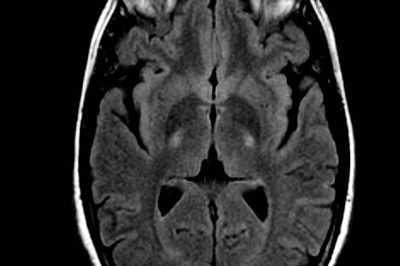

25 de Febrero de 2013 Fuente: mayoclinic.org Investigadores de la Clínica Mayo, en Jacksonville, Florida, descubrieron una proteína anormal que se acumula en el cerebro de muchos pacientes con dos desórdenes neurodegenerativos — esclerosis lateral amiotrófica, también denominada enfermedad de Lou Gehrig (ELA), y demencia frontotemporal. Ellos dicen que sus hallazgos han descubierto un potencialmente…